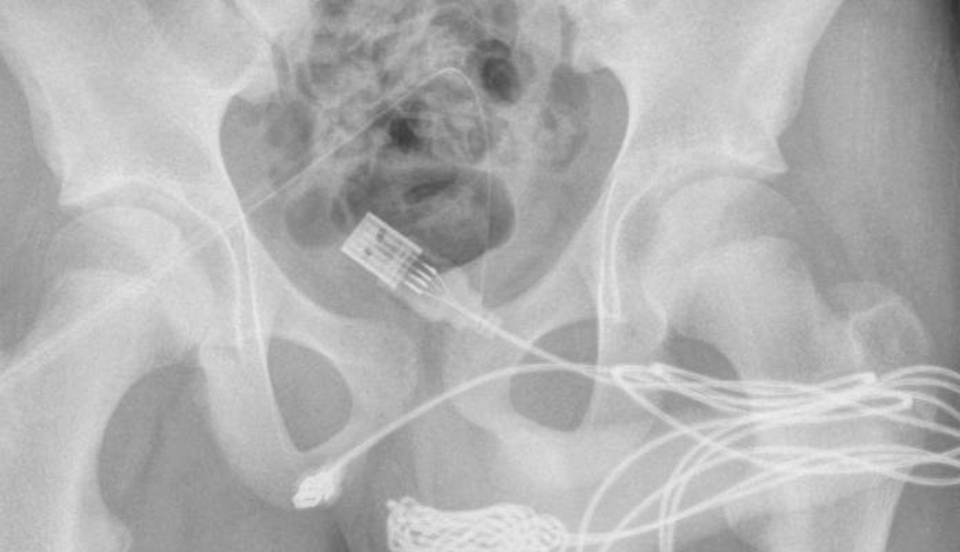

Tras escuchar su testimonio, los médicos le practicaron una radiografía pélvica simple. “Los intentos manuales y endoscópicos de extracción no tuvieron éxito, por lo que se realizó uretrostomía penoescrotal” para remover el cable, añade el papel científico.

Según la publicación Urology Case Reports, los cirujanos encargados de la operación tuvieron que hacer una incisión entre sus genitales y ano para sacar el cable.